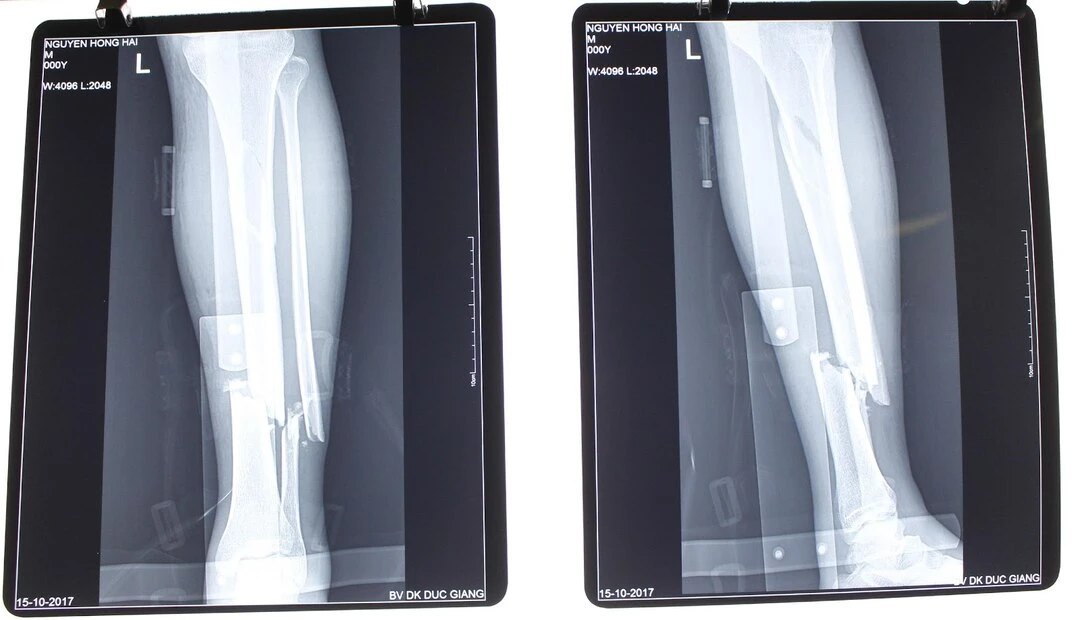

Sau khi tiến hành khám lâm sàng, bác sĩ sẽ chỉ định thực hiện chụp X-quang để xác định dạng gãy xương và mức độ tổn thương. Hình ảnh phim X-quang cho ảnh hai chiều về xương, làm lộ vết gãy và các dấu hiệu tổn thương khác. Đồng thời xác định loại và vị trí gãy.

Hình ảnh gãy chân trên phim chụp X-quang (Ảnh minh họa internet)